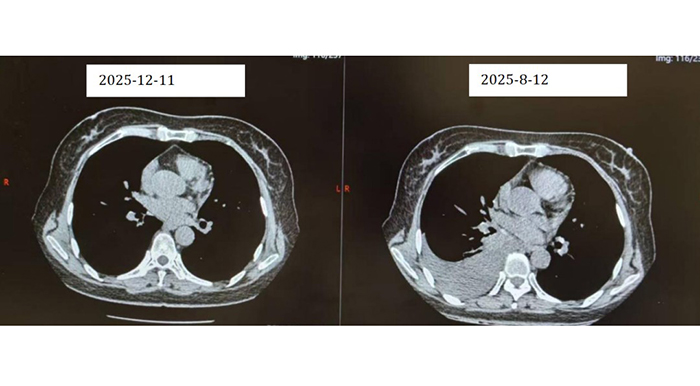

【胸科故事】一根细针揭开纵隔肿物…

一个月前,我收到胸外科同事递来的一张内镜检查申请单:36岁男性,发现“纵隔肿物”。这类患者在我院并不少见,但每一次,我都如履薄冰。打开他的胸部CT,我仔细观察肿物与食管、气管的位置关系——距离够近…